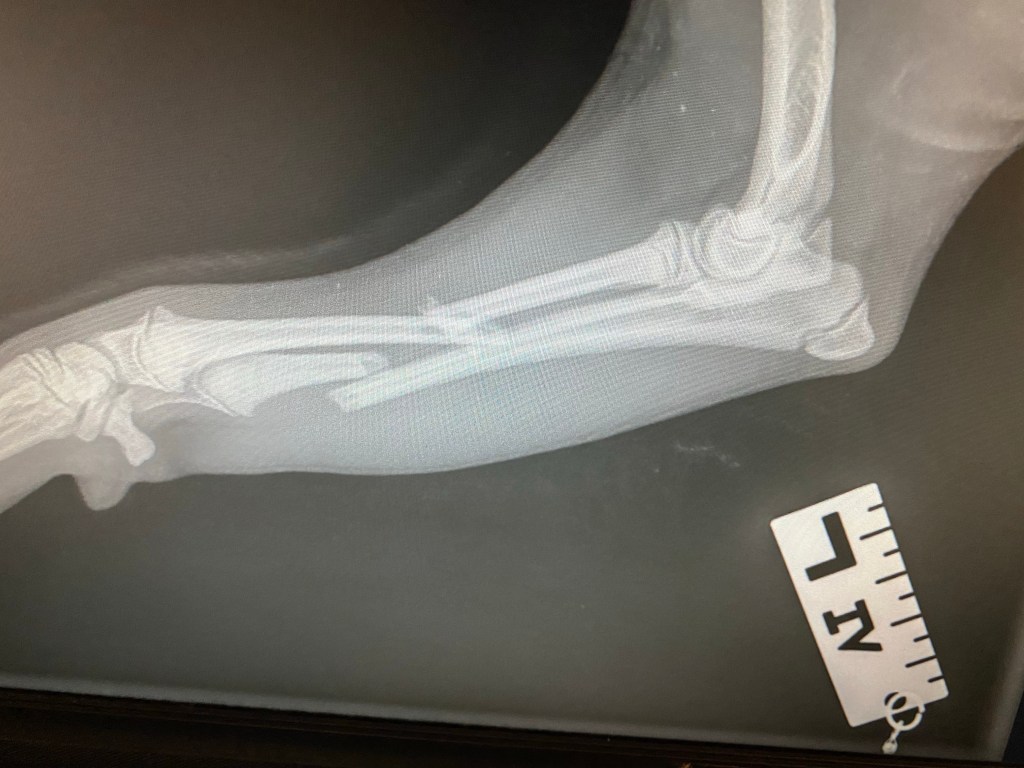

Already on my second day at work I was confronted with a 4 months old Shiba Inu with a fractured frontlimb.

With currently no orthopaedic surgeon working this far North, the owners had the option to get the limb splinted (not a good choice with this typ of fracture) or to fly the dog South to Bergen or to Oslo to get it operated. Thankfully a number of excellent specialists had visited the clinic previously, so that a lot of equipment was in fact on sight and after some hunting around for the necessary hardware, I managed to stabilise the fracture with an External Fixator (a good option with a still growing patient).